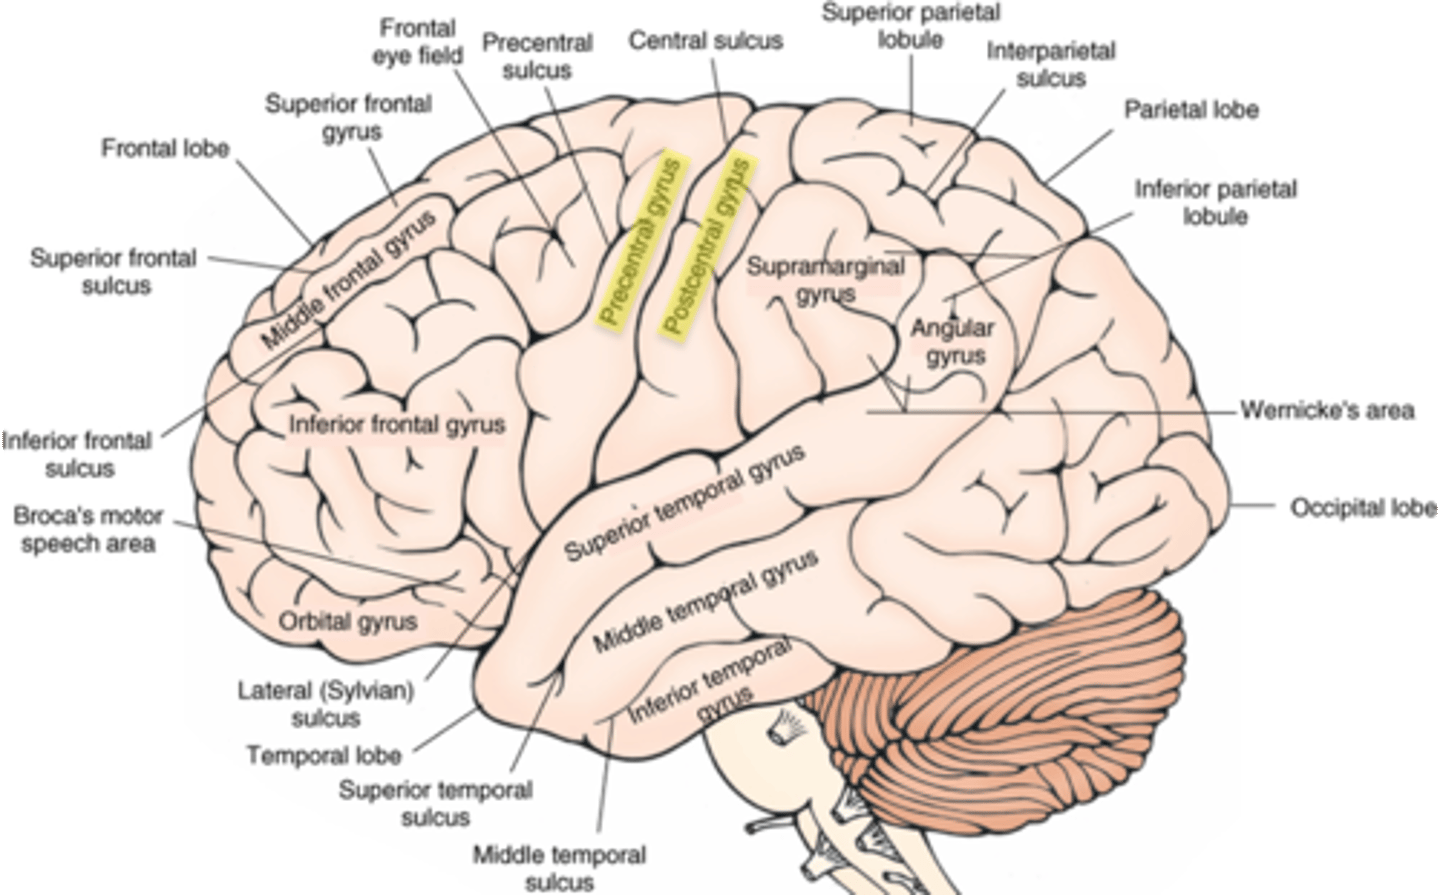

which sulcus separates the cerebral hemispheres?

longitudinal fissure

which sulcus divides the frontal lobe from the parietal lobe and divides the precentral and postcentral gyrus?

central sulcus

which sulcus divides the parietal lobe from the temporal lobe?

lateral (sylvian) sulcus/fissure

which sulcus separates the parietal lobe from the occipital lobe?

parieto-occipital sulcus

which gyrus is the primary motor complex?

precentral gyrus

which gyrus is the primary somatosensory complex?

postcentral gyrus